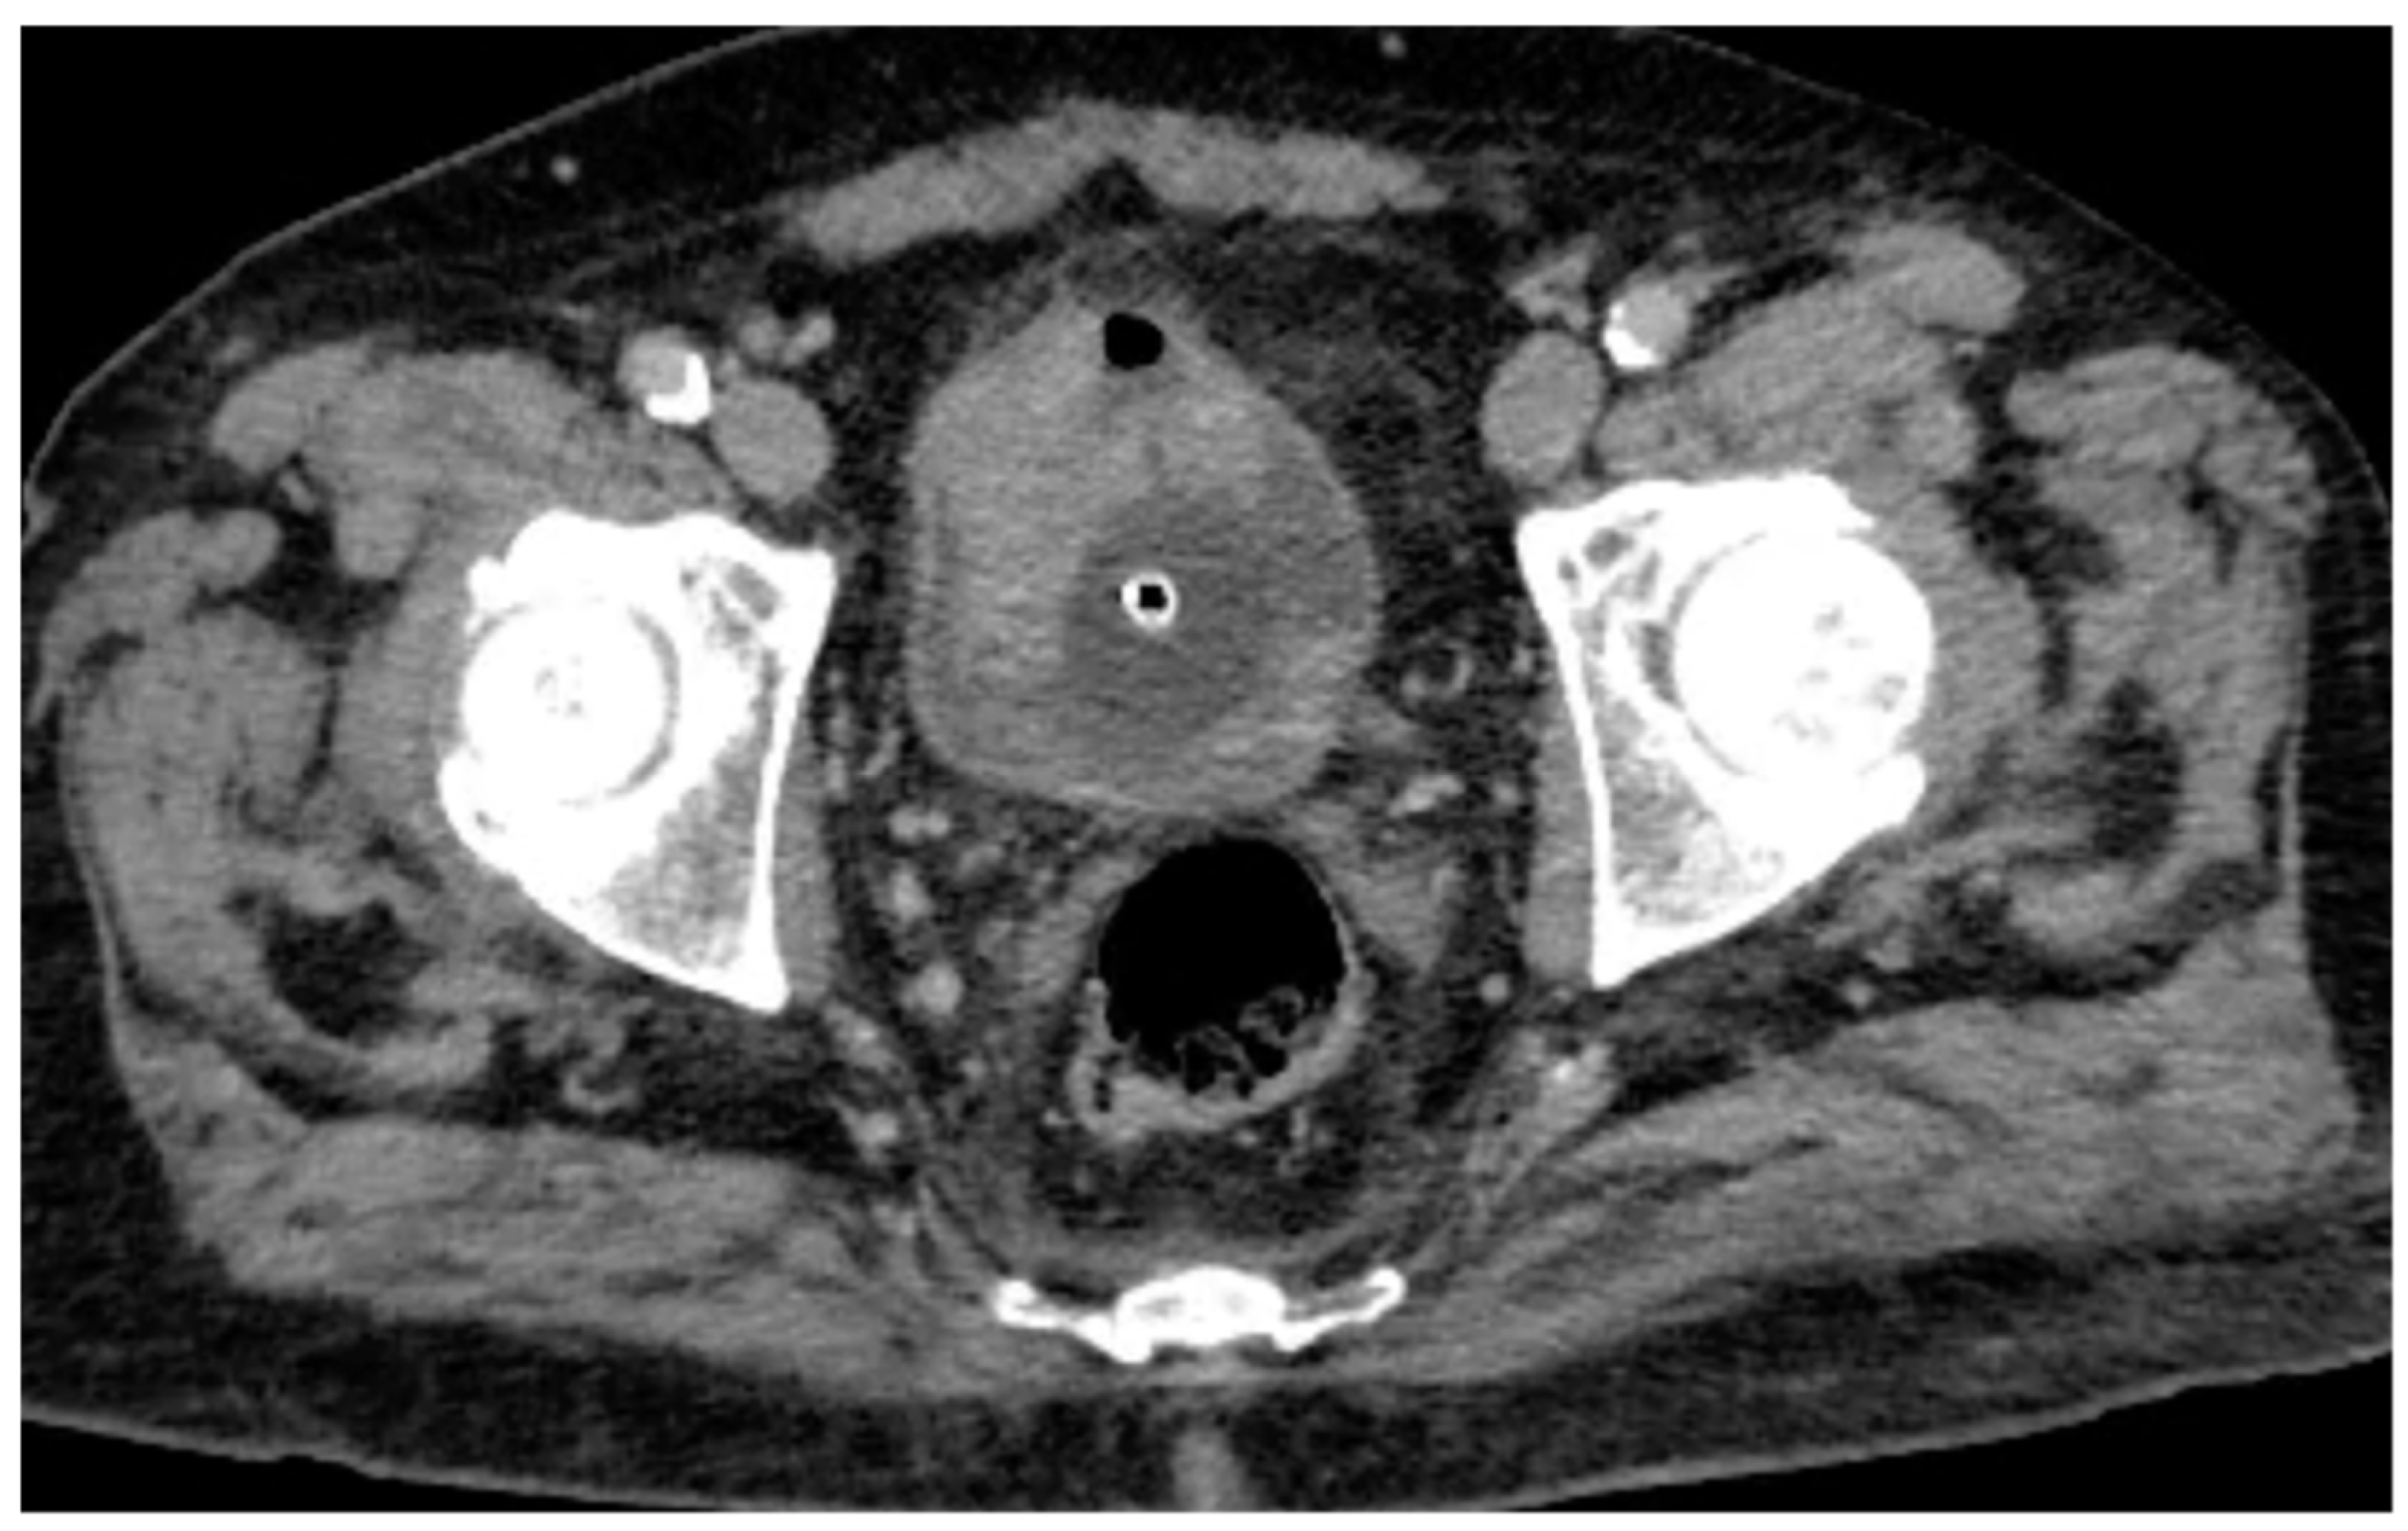

CT urography, through its multiphase protocol, enables the identification of key radiological findings that contribute to diagnostic assessment. In the conventional unenhanced phase, two hyperdense areas are observed: one along the left posterolateral bladder wall, and another protruding into the lumen at the level of the anterior wall and bladder dome (Figure 1).

Following intravenous administration of iodinated contrast medium, the venous phase confirms the presence of the hyperdense lesions along the anterior and left posterolateral bladder walls, with potential contrast enhancement that cannot be unequivocally quantified (Figure 2). Consequently, conventional CT imaging alone was insufficient to definitively characterize the nature of these findings.

Figure 1. Conventional unenhanced CT scan shows a large hyperdense lesion on the anterior bladder wall and a mildly hyperdense area along the left posterolateral wall. Further evaluation with intravenous contrast medium administration is required to better characterize these findings.

Figure 2. Venous phase CT scan confirms the previously described findings, showing a lesion involving the anterior and left posterolateral bladder wall, with an associated hyperdense intraluminal component.